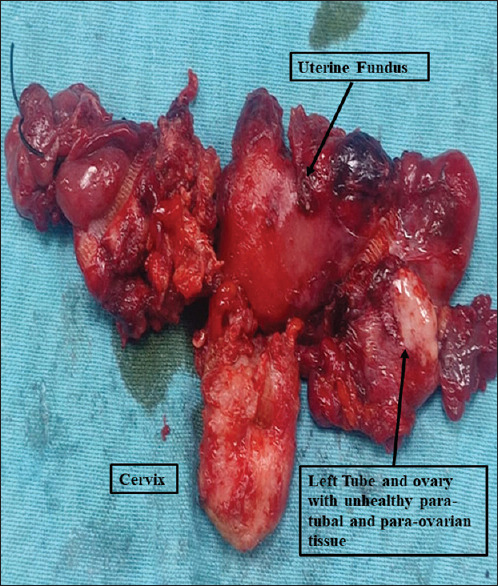

摘要浅表性宫颈鳞状细胞癌(SCC)是一种罕见的疾病,文献报道的病例很少。本病例报告简要介绍了绝经后妇女浅表性宫颈鳞状细胞癌的发现。65岁绝经后妇女,阴道出血1-2个月。经检查,子宫颈健康,无明显生长。她在磁共振成像上被诊断为子宫内膜恶性肿瘤。在子宫内膜和宫颈活检中,组织病理学显示宫颈外宫颈上皮内瘤变III型伴宫颈内膜和子宫内膜鳞状细胞癌。患者行改良根治性子宫切除术并双侧盆腔淋巴结切除术,组织病理学显示宫颈SCC浅表扩散,肿瘤细胞累及子宫内膜、子宫肌层、输卵管旁、卵巢旁、阴道边缘(未扩散至盆腔)和主动脉旁淋巴结。患者通过辅助放化疗得到了进一步的成功治疗。宫颈鳞状细胞癌是一种非常罕见的现象。它的传播不仅限于子宫内膜,而且可以扩展到子宫肌层、输卵管旁组织、卵巢旁组织和阴道组织。

Superficial spreading cervical squamous cell carcinoma (SCC) is a rare phenomenon with few cases reported in the literature. The present case report briefs the findings of superficial spreading cervical SCC in postmenopausal women. A 65-year-old postmenopausal woman presented with bleeding per-vaginum for 1-2 months. On examination, the cervix was healthy with no visible growth. She was diagnosed with an endometrial malignancy on magnetic resonance imaging. On endometrial and cervical biopsy, histopathology revealed cervical intraepithelial neoplasia III in ectocervix with SCC in endocervical and endometrial curetting. The patient underwent modified radical hysterectomy with bilateral pelvic lymphadenectomy and histopathology revealed superficially spreading cervical SCC with tumor cells involving endometrium, myometrium, paratubal, paraovarian, vaginal margins without extending to pelvic, and para-aortic lymph nodes. The patient was further managed successfully with adjuvant chemoradiotherapy. Superficial spreading cervical SCC is very rare phenomenon. Its spread is not only limited to endometrium but can extend to involve myometrium, paratubal, paraovarian, and vaginal tissues.